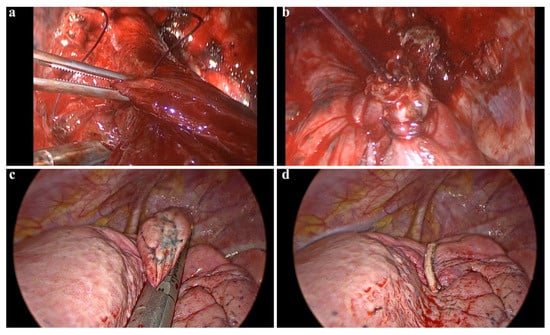

Clamp-and-Suture Group (C-group): Wedge resection was performed using a non-crushing clamp. The clamp was closed gradually, and the parenchymal lesion was excised using a scalpel. The resected lung tissue was then sutured using a U-shaped continuous running suture with 3-0 polyglactin sutures. After completing the suture, the clamp was removed, and aerostasis was tested (Figure 2a).

Figure 2. Surgical technique and postoperative management in VATS wedge resection. (a,b) Demonstrate the lung parenchyma being grasped with a clamp and subsequently sutured following a wedge resection. This clamp-assisted suturing technique can be utilized in atypical locations where the placement of an automatic stapler device is challenging. (c,d) Illustrate images of a wedge resection performed using an endoscopic parenchymal stapler device.

2.6. Postoperative Drainage

Postoperative chest radiography was performed within three hours of transfer to the ward to assess lung expansion (Figure 2c). On postoperative day one, chest tubes were removed in patients who met the following criteria: